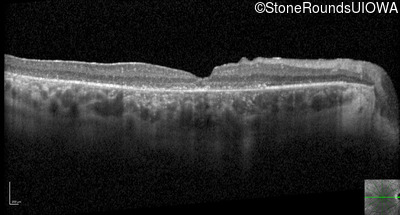

Optical Coherence Tomography - Left - 20/125 -1

Exemplar / OCT Stack

OCT Stack